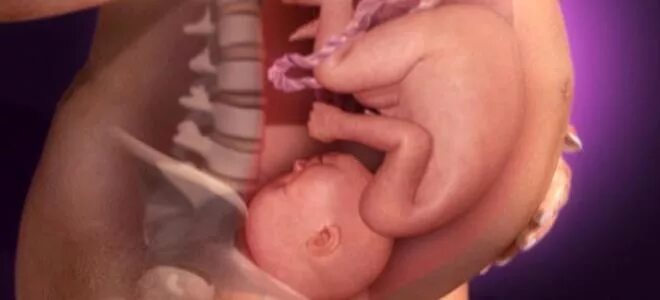

Ребенок в 20 недель беременности в животе